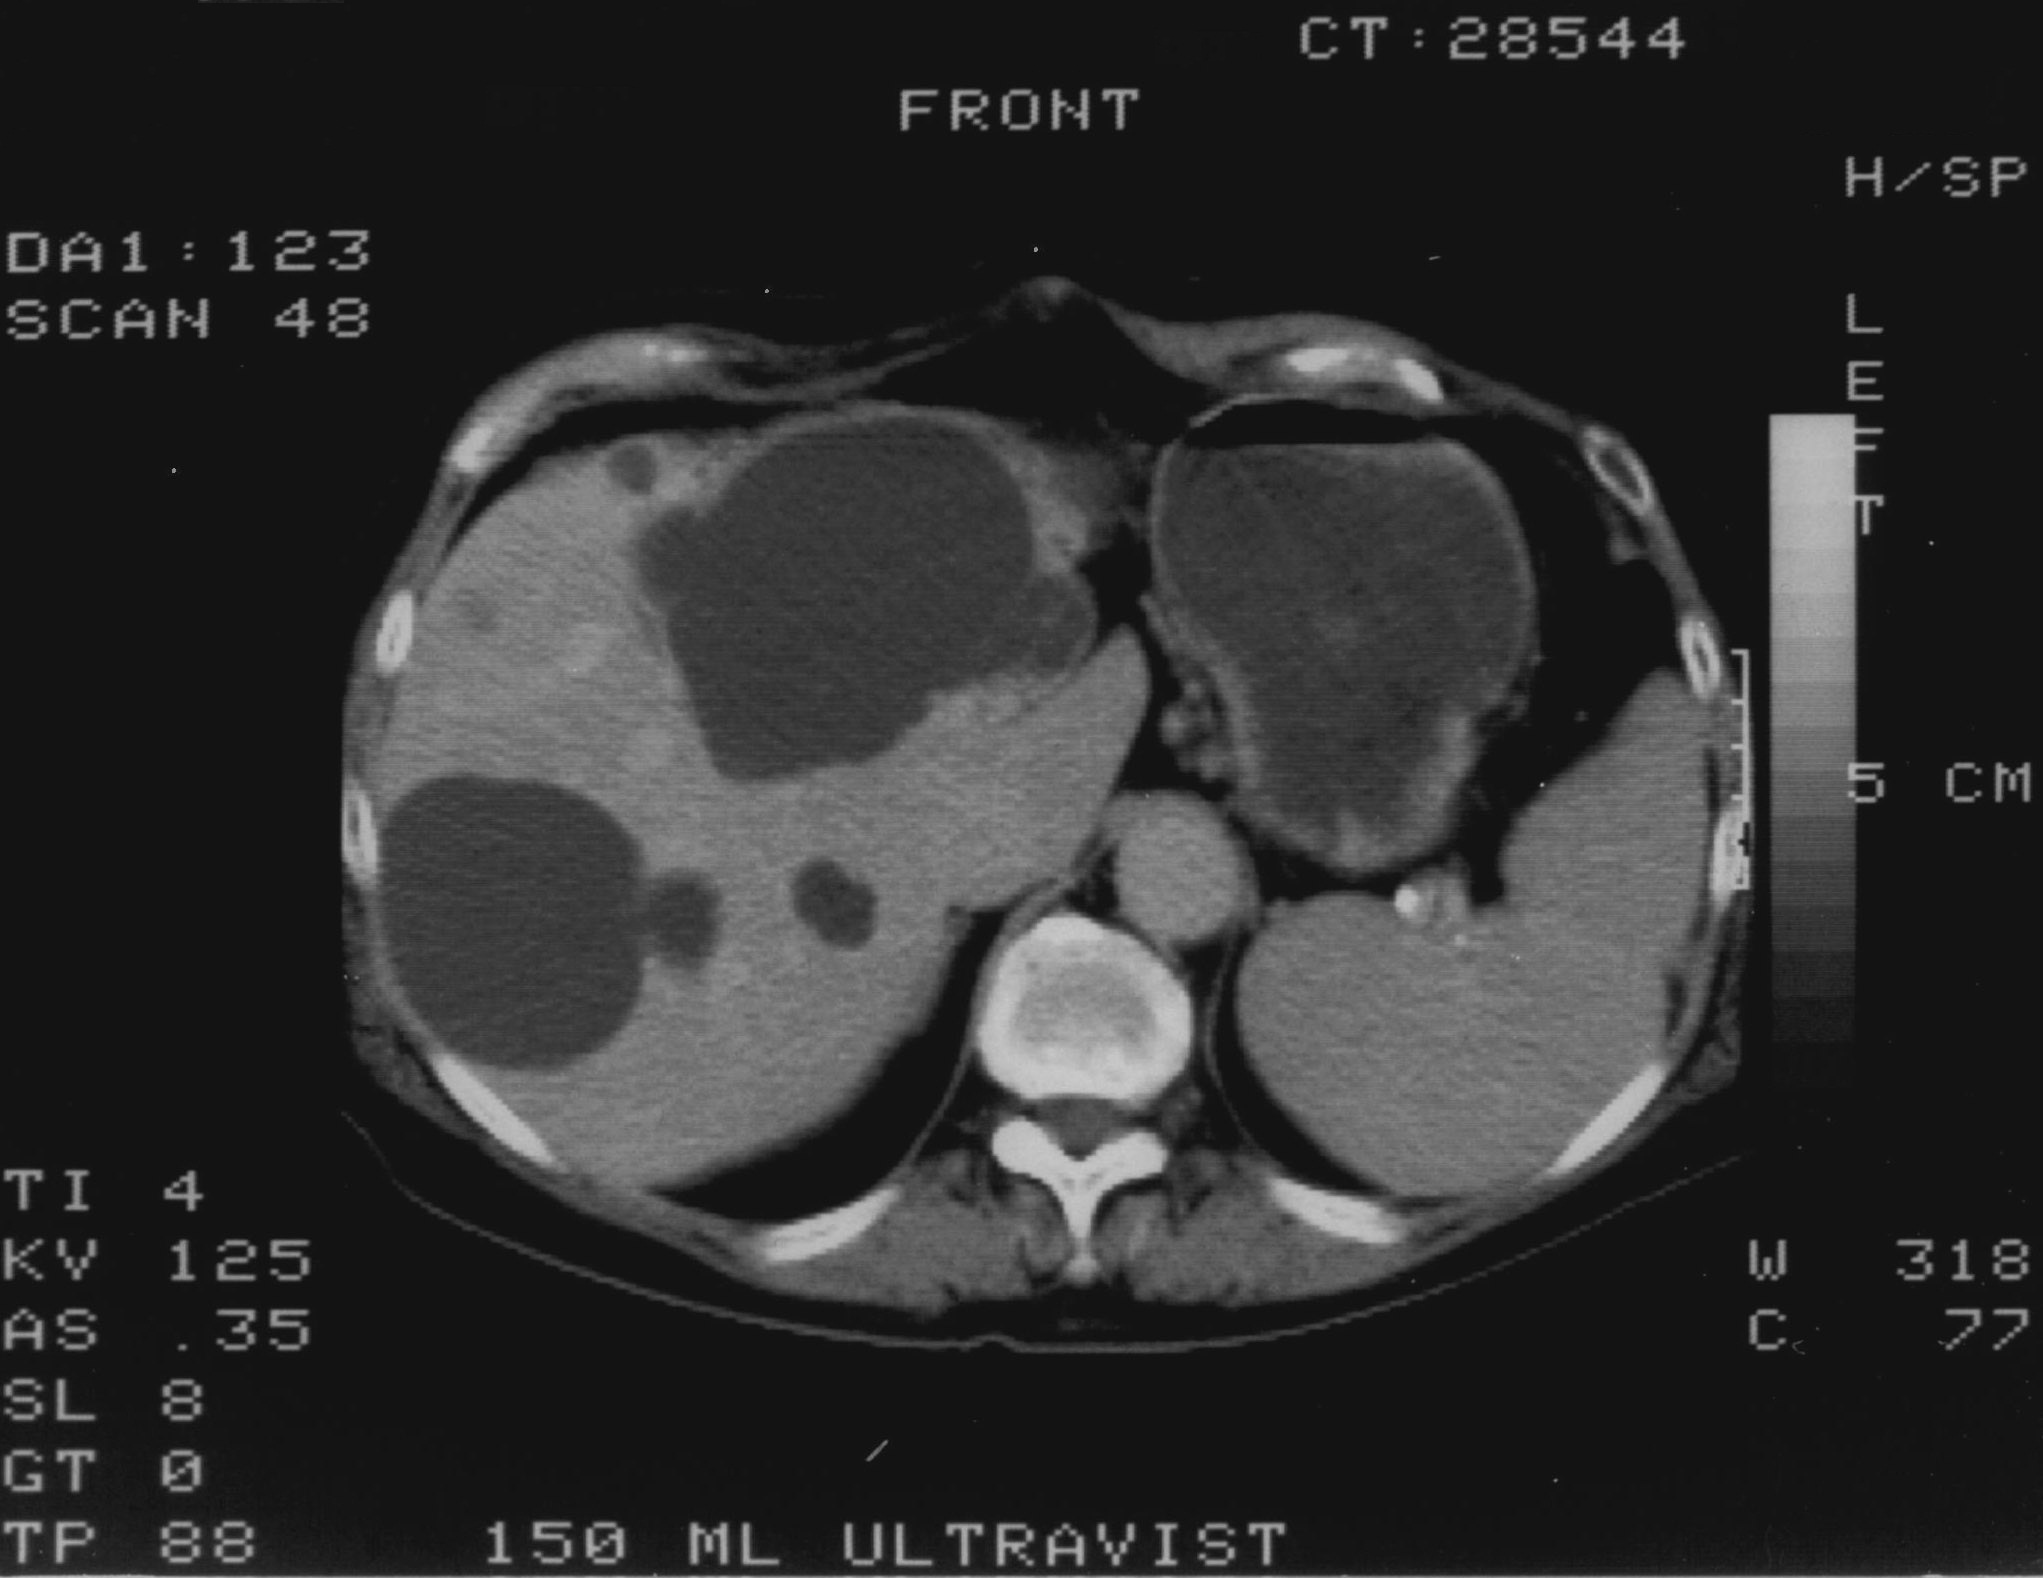

Compared to the surgical methods of past, nowadays these cystic lesions can be successfully treated percutaneously with alcoholic cyst sclerotization. (Figures 26., 27.).

Image

Figure 26. – Percutaneous ethanol cyst sclerotization ( filling up of the cyst before the sclerotization)

Figure 27. – US and CT examinations before percutaneous ethanol sclerotization (A: US examination, B: CT examination)

The puncture of the cyst is usually guided with US (rarely with CT). The puncturing needs to take place from the parenchymal side of the cyst. When its contents are removed the empty cavity is filled up with diluted contrast material to ensure that there is no contrast leakage to the surroundings. The 96% ethanol is only injected after the contrast material has been removed and no leakage was found. (The volume of the alcohol should not exceed 50-60% of the cyst or 100 ml.)

The injected ethanol is left in the cyst for 20 minutes. Following this, the alcohol is drained as well. Cystic regression is then regularly controlled with US or CT examinations. (Figures 28., 29.) Patient complaints usually cease within 4-6 weeks after the treatment.

Figure 28. – Control CT examination after percutaneous ethanol liver cyst sclerotization (9 months later) – significant regression

A

B

Figure 29. – Percutaneous ethanol hepatic cyst sclerotization, CT examinations (A: before treatment, B: 6 months after treatment ) – pronounced regression